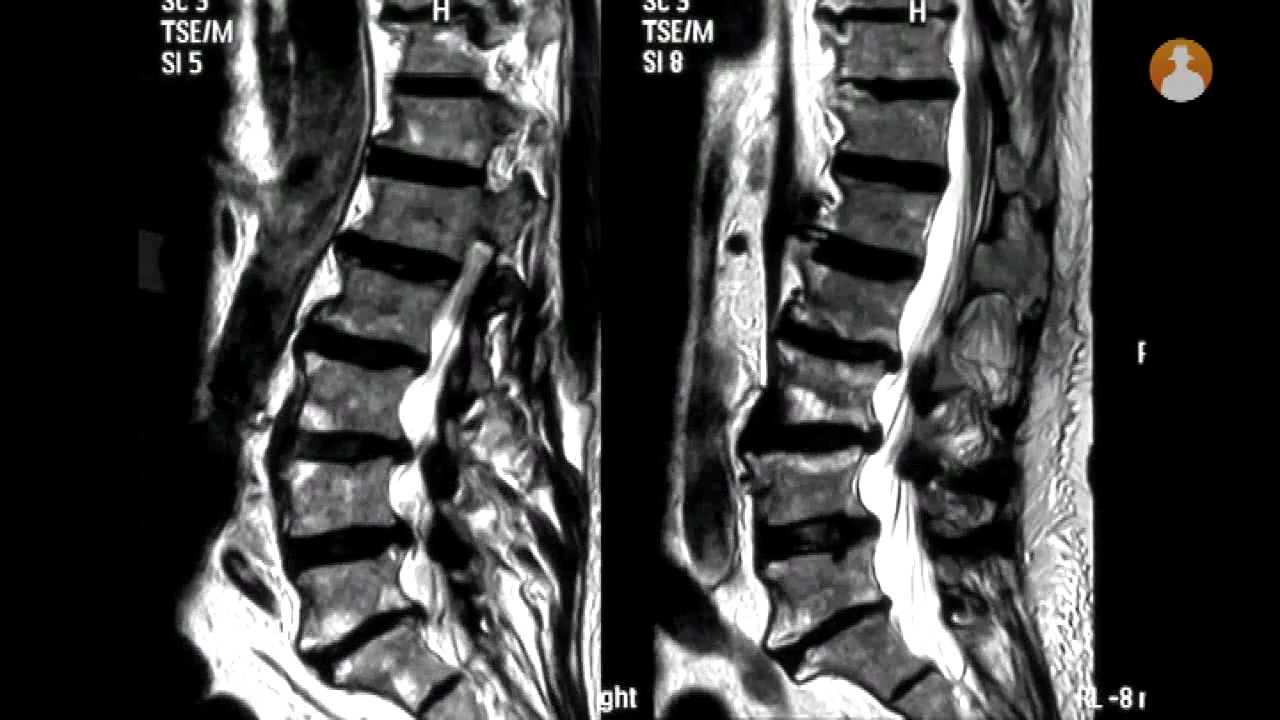

Los principales problemas en estas edades son las estenosis de canal, las fracturas o la inestabilidad vertebral. Para tratarlas, se utilizan técnicas poco agresivas e invasivas como la cirugía percutánea. Así, las intervenciones quirúrgicas duran menos tiempo y la recuperación del paciente es más rápida. Unas ventajas que también han sido referidas el doctor Marcelo Budke, neurocirujano de la Unidad de Neurocirugía de la Clínica La Luz, durante la rueda de prensa.

Actualmente, con la práctica de estas cirugías percutáneas el enfermo al día siguiente se va a su casa y puede comenzar a hacer vida normal. Algo que ha certificado Luis Valles López, un paciente de 84 años que se ha sometido a la cirugía. Los expertos reunidos han coincidido que la edad no es una barrera para poder mejorar la calidad de vida del paciente aunque para lograrlo tenga que operarse.